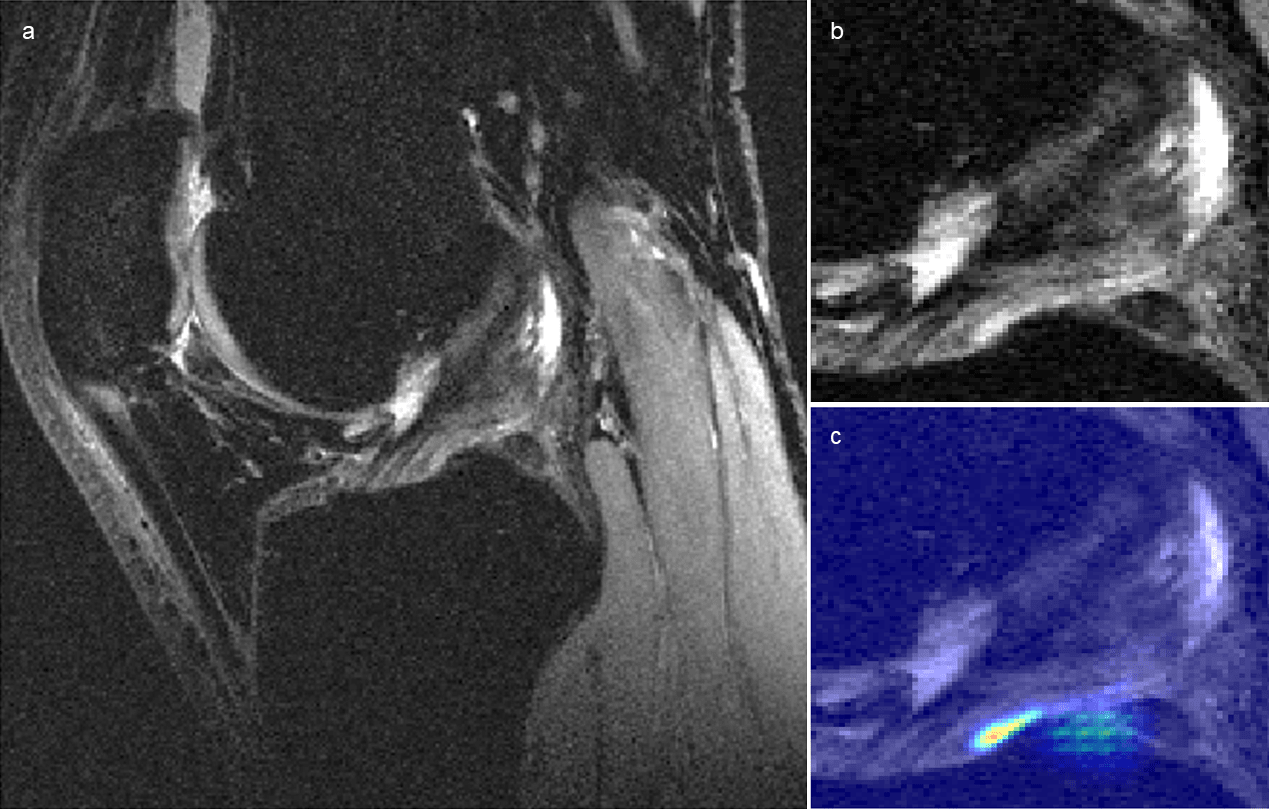

Figure 5 displays a knee with intact ACL that was input into the pipeline, followed by localization of the ACL and the corresponding saliency map generated by the model’s classification weighting. Saliency maps were generated from the 3D CNN’s rectified linear unit output in its last dense layer. This ACL was correctly classified and possesses a high intensity on the inferior portion of the ligament’s saliency. An incorrectly classified intact ACL, predicted to be partially torn, is seen in Figure 6. The model placed a high intensity on a sagittal view with overlapping ACL and femur signal. The resulting saliency possessed large weight on a portion of the joint posterior to the ligament and also has speckles of noise further posterior. The 3D CNN took less than one second to classify a single ACL that went through all three hierarchical classifiers.

Refer to caption

Figure 6: Sagittal views of (a) incorrectly classified knee with intact anterior cruciate ligament (ACL) and (b) its ACL localization with (c) overlaid saliency map. The model predicted a partial tear in this knee. The model misplaces a relatively high probability mapping on a slice with ACL that is obstructed by signal from femur. Additionally, the saliency intensity is posterior to the actual ligament; speckles of noise are also present in the inferior-posterior portion of the saliency. This intact ACL possessed focal fluid collection posterior to the ligament on a separate sagittal view, which may have led to the misclassification.